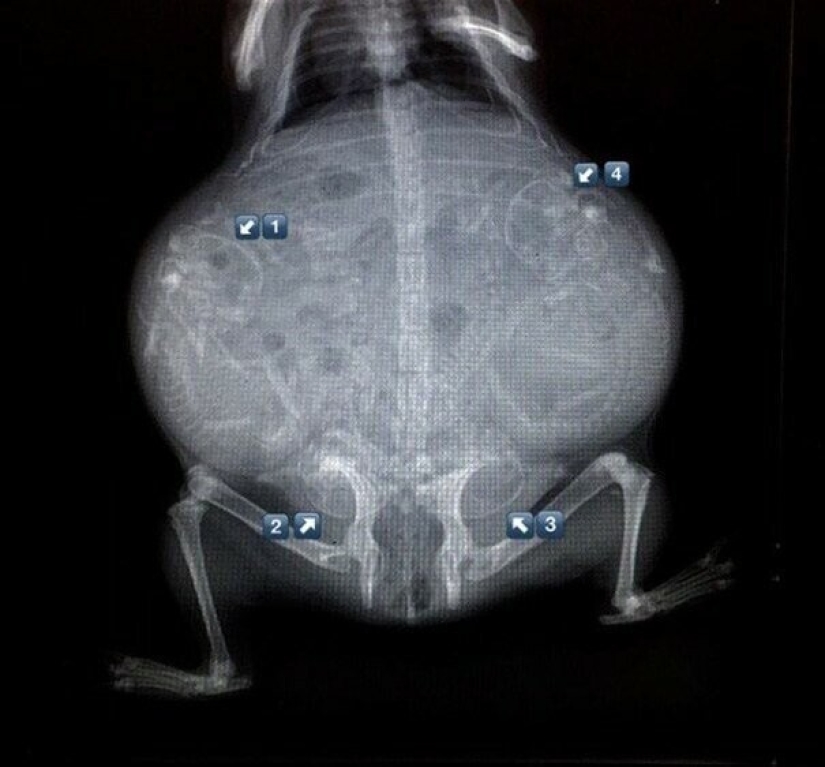

Conejillo de Indias embarazada